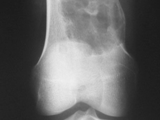

SCFE-Hips

SCFE-Hips